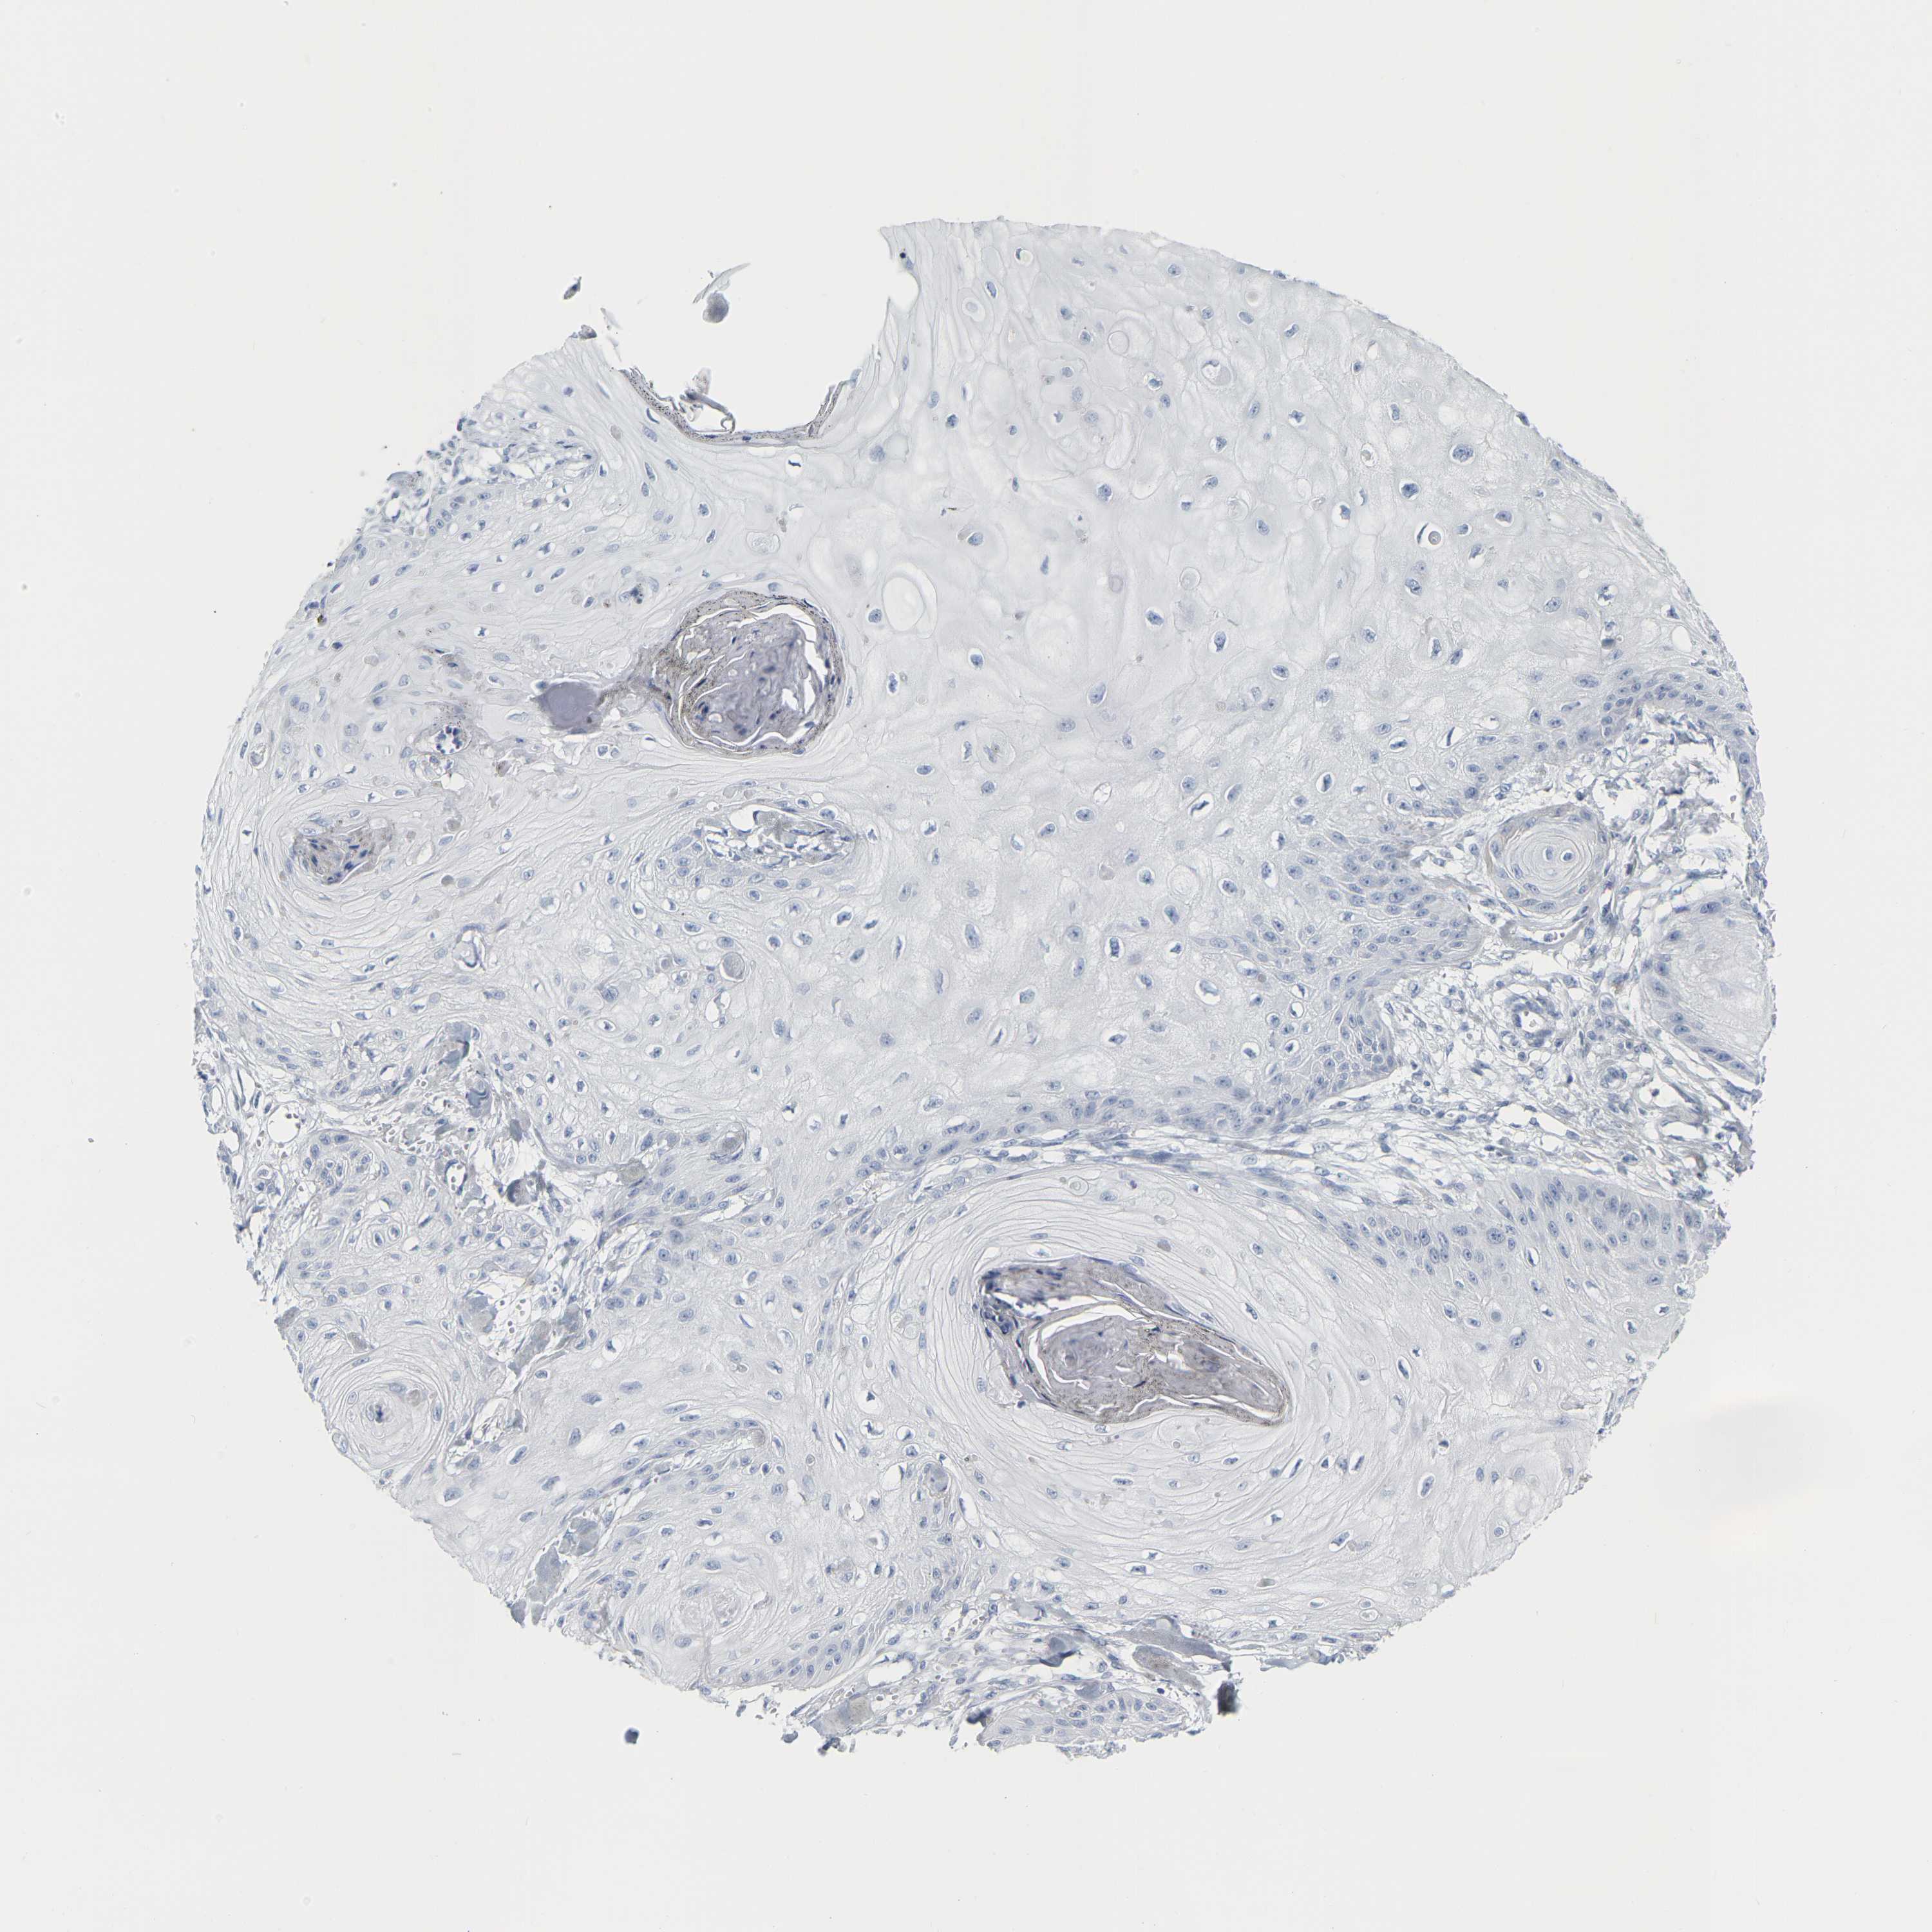

SKIN CANCER - Protein expressioni

A mouse-over function shows sample information and annotation data. Click on an image to view it in a full screen mode. Samples can be filtered based on level of antibody staining by selecting one or several of the following categories: high, medium, low and not detected. The assay and annotation is described here.

Each image is clickable and will lead to virtual microscopy that enables deeper exploration of all samples and also displays staining intensity scores, fraction scores and subcellular localization as well as patient and tissue information for each sample.

Antibody HPA027478

Staining

High

Medium

Low

Not detected

Intensity

Strong

Moderate

Weak

Negative

Quantity

>75%

75%-25%

<25%

None

Location

Nuclear

Cytoplasmic/membranous

Cytoplasmic/membranous,nuclear

Squamous cell carcinoma, NOS